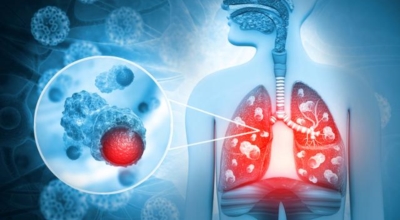

폐에 발생된 악성 종양을 말하며 오랜 기간 흡연해온 남성들에서 발병률이 높고 최근 들어 가지가지 환경적인 요인의 영향과 간접흡연으로 흡연하지 않는 여성에서도 많이 발생하고 있어요. 증상을 느껴 병원을 찾았을 때는 수술하기 늦은 경우가 많아 사망하는 비율이 매우 높은 암입니다. 폐 자체에서 생기거나 다른 장기에서 발생된 암이 폐로 전이되어 나타나기도 하고 특별한 초기 증상이 없는 경우가 많다고 하며 암이 진행된 후에도 일반적인 감기 증상인 기침과 가래 외의 특이 증상이 나타나지않아 증상만으로는 진단이 쉽지 않아요.

폐암 역시 다른 암들과 마찬가지로 조기 발견 및 치료가 매우 중요하므로 일상 속에서 폐암 초기증상을 간과하지 않도록 주의를 기울여야 해요. 따라서 긴 시간의 흡연, 간접흡연에 노출됐거나 평상시 폐 기능이 좋지 않고 호흡기 질환에 잘 걸리는 예민한 편이라면 폐암 초기증상에 관하여 잘 알아뒀다가 이상이 있다고 생각되면 최대한 빨리 전문의를 찾아 정확한 검진을 받아보는 편이 좋아요.